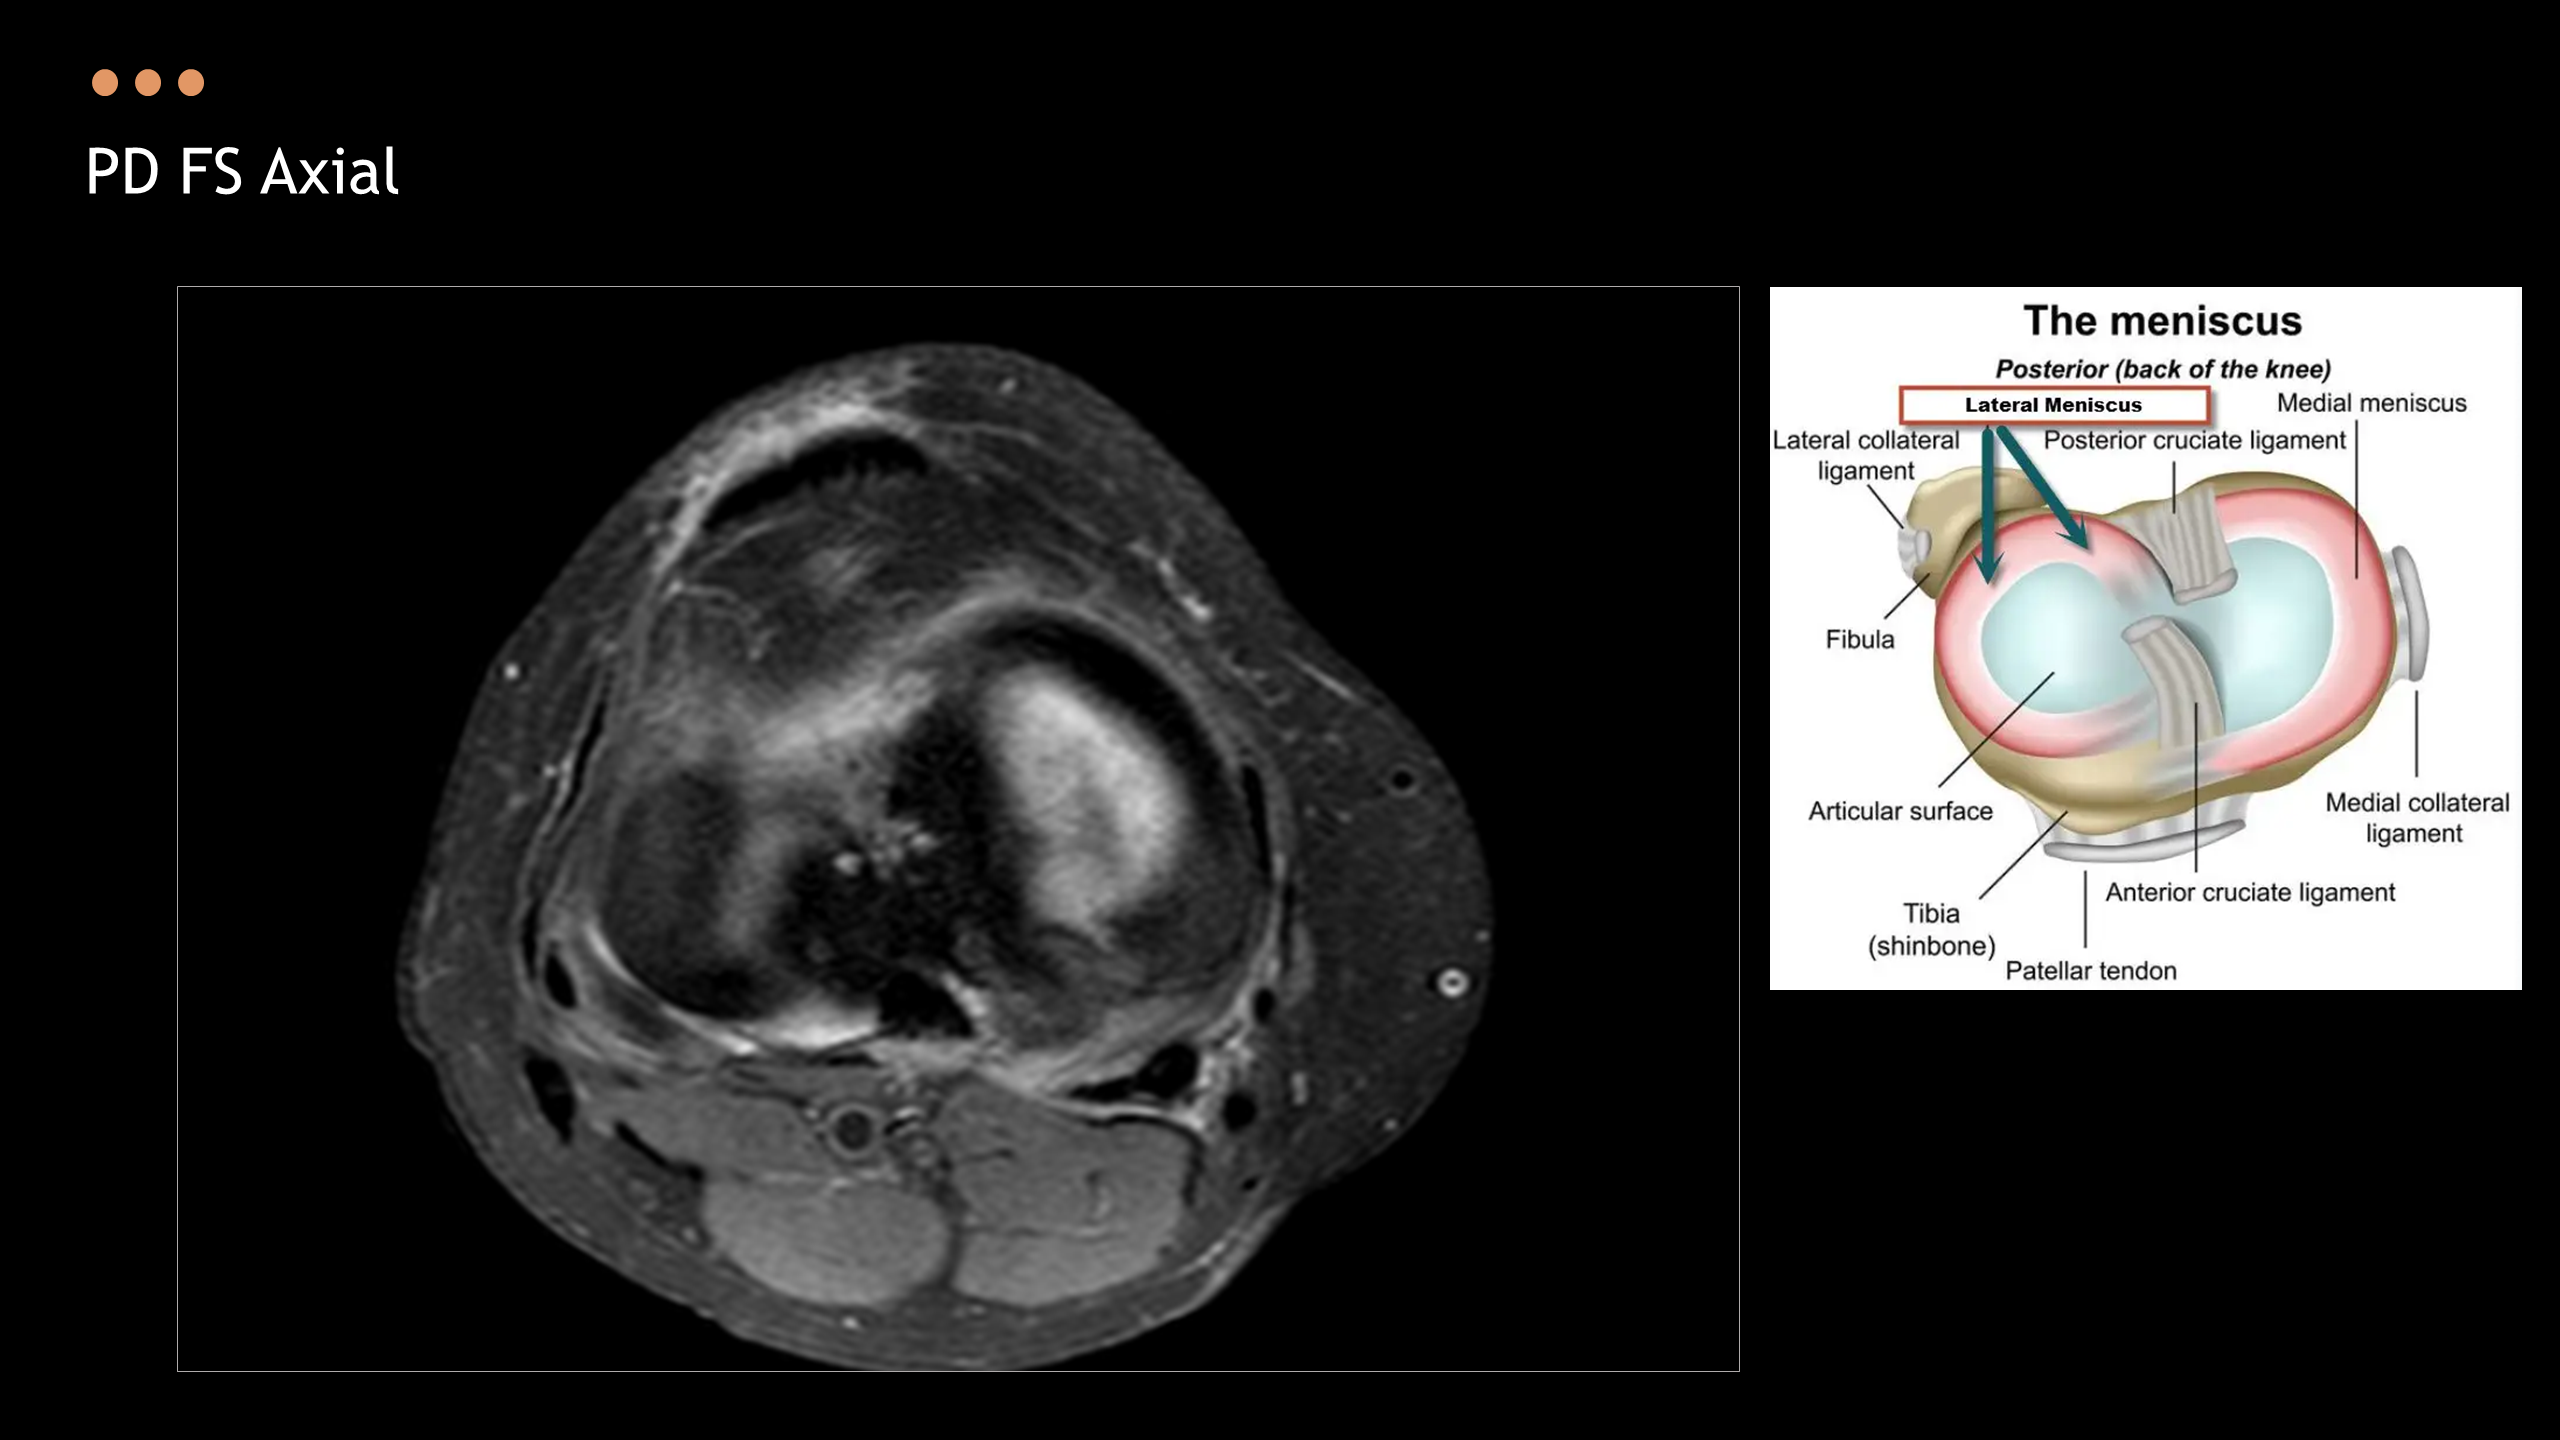

아래의 Normal Knee MR Anatomy를 숙지하고 오셔야, 강의에 어려움이 없습니다.

Detailed Knee MRI Anatomy [대한연부조직한의학회].pdf